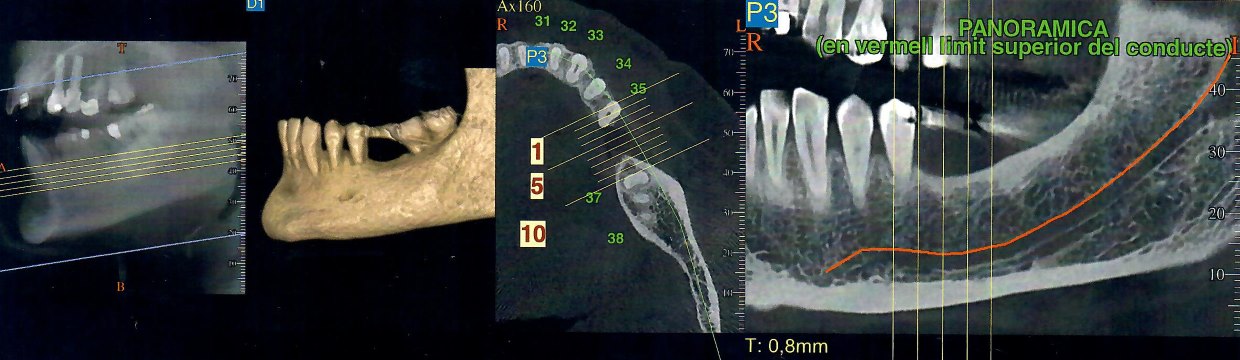

Gran parte delle chirurgie implantarí le eseguiamo con la visualizzazione di un Dentalscan orale grazie alla collaborazione diretta con il centro radiologico RADMEDICA pioniero in Italia e Spagna delle TAC in 3 dimensioni.

La TAC DENTALSCAN 3D comporta fino allo 80% di radiazioni in meno rispetto le tac tradizionali. Il Dentalscan è il programma che si utilizza per ricostruire sul computer le arcate dentarie dopo aver effettuato la tac e ci consente di fare una vera e propria ricostruzione delle ossa del nostro cavo orale e mascellare e dei tessuti molli della bocca in immagini tridimensionali, evidenziando anche l’espansione di eventuali processi nascosti infiammatori e fornendo precisioni millesimali ai fini della collocazione degli impianti dentali.